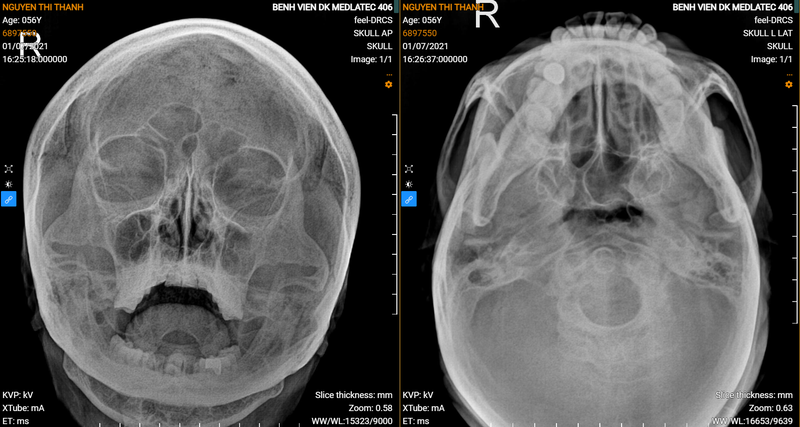

Chụp X-quang theo Blondeau còn được gọi là tư thế chụp mũi - cằm - phim. Tư thế này giúp bộc lộ rõ cấu trúc nền sọ, xương chẩm có hình ở phía dưới cũng như các xoang mặt (gồm xoang trán, xoang sàng, xoang hàm…) và hố mắt. Tư thế chụp Blondeau cũng phản ánh cung tiếp xương gò má, xương hàm dưới.

Theo tư thế này, bệnh nhân được yêu cầu nằm sấp, sau đó đặt mũi và cằm chạm vào phim chụp, đồng thời cần há miệng tối đa. Tia X sẽ được chiếu từ phía sau ra đằng trước. Để thu được hình ảnh chụp X-quang chính xác và rõ nét, phim chụp cần được đặt cân đối giữa 2 bên phải và trái.